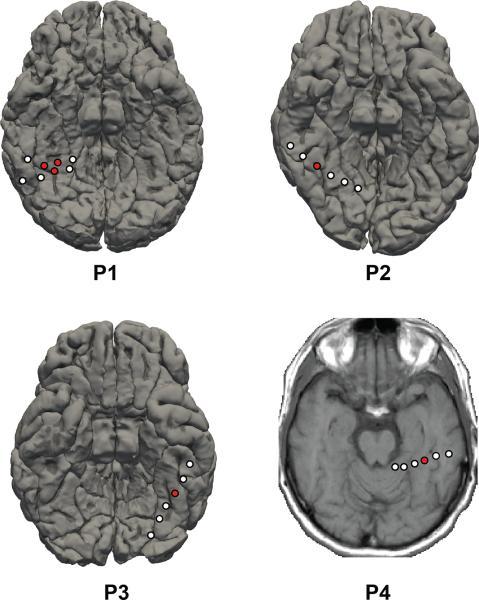

Humans' ability to rapidly and accurately detect, identify and classify faces under variable conditions derives from a network of brain regions highly tuned to face information. The fusiform face area (FFA) is thought to be a computational hub for face processing; however, temporal dynamics of face information processing in FFA remains unclear. Here we use multivariate pattern classification to decode the temporal dynamics of expression-invariant face information processing using electrodes placed directly on FFA in humans. Early FFA activity (50-75 ms) contained information regarding whether participants were viewing a face. Activity between 200 and 500 ms contained expression-invariant information about which of 70 faces participants were viewing along with the individual differences in facial features and their configurations. Long-lasting (500+ms) broadband gamma frequency activity predicted task performance. These results elucidate the dynamic computational role FFA plays in multiple face processing stages and indicate what information is used in performing these visual analyses.